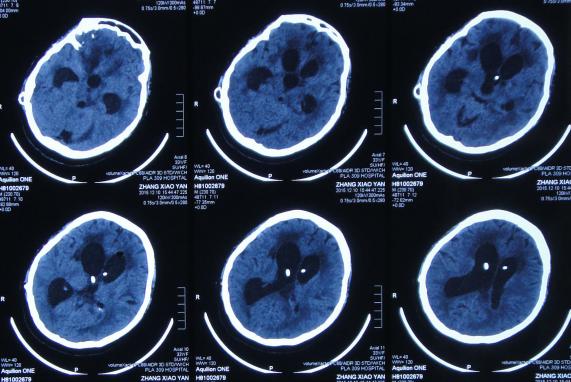

2016年6月3日住入李小勇脑脊液中心,入院时:卧床,反应慢,表情淡漠,言语迟钝(问答无反应),吞咽困难,只能鼻饲流食,头部有多处手术疤痕,右下肢自主活动差,但刺激后能动(图-25);入院第2天即2016年6月5日,头部CT示脑积水,脑室粘连,脑萎缩(图-26)。

图-26:2016年6月5日头部CT入院时

入院后4天即2016年6月7日,进行了脑室腹腔分流管取出术+脑室腹腔分流泵取出术+脑室外引流术+脑室腹壁外引流术+透明隔造瘘术,术后当天查头部CT示脑室引流术后(图-27)。

图-27:2016年6月7日术后头部CT

入院治疗2个月时间内,虽脑室缩小,但仍有结核性脑脓肿(图-28、图-29),且病情持续加重致昏睡,不能遵嘱活动,不能言语。